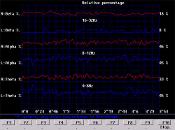

Porcentagem relativa de Beta – Alpha – Theta

As imagens comparam as percentagens esquerdo / direito como um total no eixo vertical direito e tempo (por segundo) no eixo horizontal.

Equilíbrio entre hemisférios esquerdo e direito em Beta – Alpha – Theta

Estas imagens mostram a cooperação entre os hemisférios direito e esquerdo do cérebro, ou seja, o equilíbrio, separados em frequências Beta – Alpha – Theta. A linha amarela mostra o grau do equilíbrio. Uma linha reta mostra o equilíbrio perfeito.